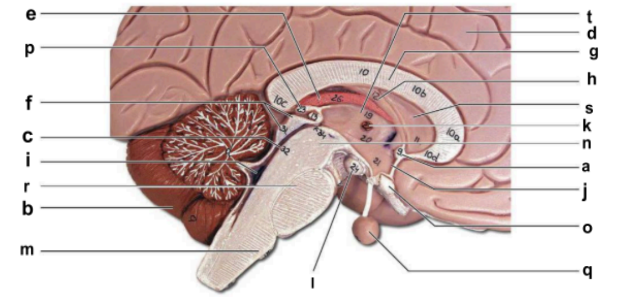

Identify the structure labeled “a” in the image.

anterior commissure

Identify the structure labeled “b” in the image.

cerebellum

Identify the structure labeled “c” in the image.

cerebral aqueduct

Identify the structure labeled “d” in the image.

cerebral hemisphere

Identify the structure labeled “e” in the image.

choroid plexus

Identify the structure labeled “f” in the image.

corpora quadrigemina

Identify the structure labeled “g” in the image.

corpos callosum

Identify the structure labeled “h” in the image.

fornix

Identify the structure labeled “i” in the image.

fourth ventricle

Identify the structure labeled “j” in the image.

hypothalamus

Identify the structure labeled “k” in the image.

interthalamic adhesion

Identify the structure labeled “l” in the image.

mammilary body

Identify the structure labeled “m” in the image.

medulla oblongata

Identify the structure labeled “n” in the image.

midbrain

Identify the structure labeled “o” in the image.

optic chiasma

Identify the structure labeled “p” in the image.

pineal gland

Identify the structure labeled “q” in the image.

pituitary gland

Identify the structure labeled “r” in the image.

pons

Identify the structure labeled “s” in the image.

septum pellucidum

Identify the structure labeled “t” in the image.

thalamus